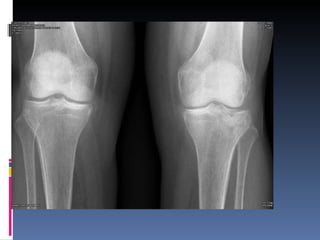

Osteoartritis IFDs, IFPs, 1 st  CMC Osteofitos Estrechez asimetrica del espacio articular  Esclerosis subcondral Quistes subcondrales No erosiones marginales Densidad osea preservada

Osteoartritis

Osteoartritis IFDs, IFPs,1 st CMC Osteofitos Estrechez asimetrica del espacio articular Esclerosis subcondral Quistes subcondrales No erosiones marginales Densidad osea preservada